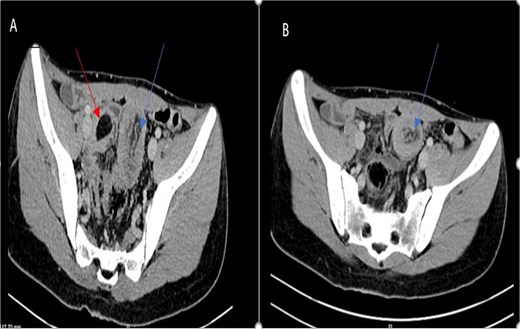

Laboratory findings were within normal ranges. Abdominal CT revealed a telescoping intestine measuring 20 × 4 cm, with an intraluminal lesion displaying fat-density at 15 × 25 mm (Fig. 1), surrounded by the thick-walled intussuscipiens (Fig. 2). No significant proximal bowel dilation or additional lesions were observed.

Axial CT scan showing an oval fat density mass representing a jejunal lipoma (A) and a telescoping intestine measuring 20 × 4 cm (B).

These findings led to a diagnosis of intussusception induced by a jejunal lipoma.